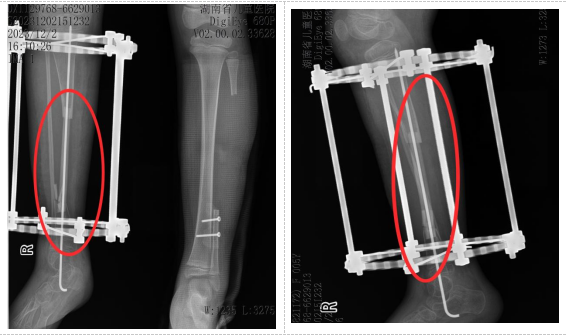

术后

小小出生3个月时即发现右小腿下段弯曲,2岁时因胫骨骨折辗转于数家医院,经多次手术失败后经人推荐来湖南省儿童医院治疗。先天性胫骨假关节导致小小右侧胫骨出现大段骨缺损,传统治疗方法效果有限,且存在肢体短缩、畸形甚至截肢的风险。面对这一棘手难题,湖南省儿童医院骨科团队经过多次病例讨论和精密规划,决定实施一项新的手术方案:“右侧胫骨内固定取出,右侧胫骨假关节病变切除,取左侧带血管蒂的腓骨移植,克氏针髓内固定,伊氏架外固定,左侧胫腓骨远端融合,石膏托外固定术”。即从小小健康的左侧小腿取一段带血管蒂的腓骨,移植到右侧胫骨缺损处,通过吻合血管重建移植后的腓骨血运,重建胫骨的完整性与支撑功能。

在麻醉手术科的密切配合下,以谭谦主任医师、王军主治医师为核心的手术团队历时数小时,凭借精湛的显微外科技术和丰富的骨科经验,顺利完成供区腓骨切取、受区准备、骨骼固定及血管吻合等一系列高难度步骤。术后,小小在骨科团队的精心护理和指导下,顺利出院。